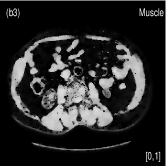

We also evaluated the proposed PWLS-TNV- method using clinical pelvis data. The patient’s pelvis data was acquired by Siemens SOMATOM Definition flash CT scanner using DECT imaging protocol. Table 4 lists acquisition parameters in the pelvis data scan. Fig. 5 shows the high- and low-energy CT images of the pelvis data. Fig.5 (b) shows selected basis materials, bone, iodine, muscle, fat and air, and their assosicated ROIs highlightened in white dashed line circles. We implemented the Direct Inversion method in mendonca2014a and used its results as the initialization for the PWLS-EP-LOOP xue2017statistical and the proposed PWLS-TNV- method. Fig. 6 shows the decomposed material images by the Direct Inversion, the PWLS-EP-LOOP and the PWLS-TNV- method. Table 5 summarizes the means and noise STDs of the decomposed material images by the above three methods. The volume fraction (VF) accuracies are , , and for the Direct Inversion method, the PWLS-EP-LOOP method and the proposed PWLS-TNV-, respectively. Compared with the Direct Inversion and PWLS-EP-LOOP method, the proposed method improves the VF accuracy by and respectively. The proposed PWLS-TNV- method decomposes basis material images more accurately, suppresses noise and decreases crosstalk, while retaining spatial resolution of the decomposed images compared to the other two methods.